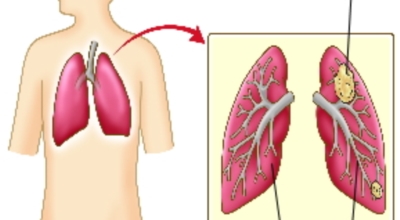

폐에 발생된 악성 종양을 말하며 오랜 기간 흡연해온 남성들에서 발병률이 높고 요즘 들어 가지가지 환경적인 요인의 영향과 간접흡연으로 흡연하지 않는 여성에서도 많이 발생하고 있어요. 증상을 느껴 병원을 찾았을 때는 수술하기 늦은 경우가 많아 사망하는 비율이 매우 높은 암입니다.

폐 자체에서 생기거나 다른 장기에서 발생된 암이 폐로 전이되어 나타나기도 하고 특별한 초기 증상이 없는 경우가 많다고 하며 암이 진행된 후에도 일반적인 감기 증상인 기침과 가래 외의 특이 증상이 나타나지않아 증상만으로는 진단이 쉽지 않아요. 폐암 역시 다른 암들과 마찬가지로 조기 발견 및 치료가 매우 중요하므로 일상 속에서 폐암 초기증상을 간과하지 않도록 주의를 기울여야 해요.